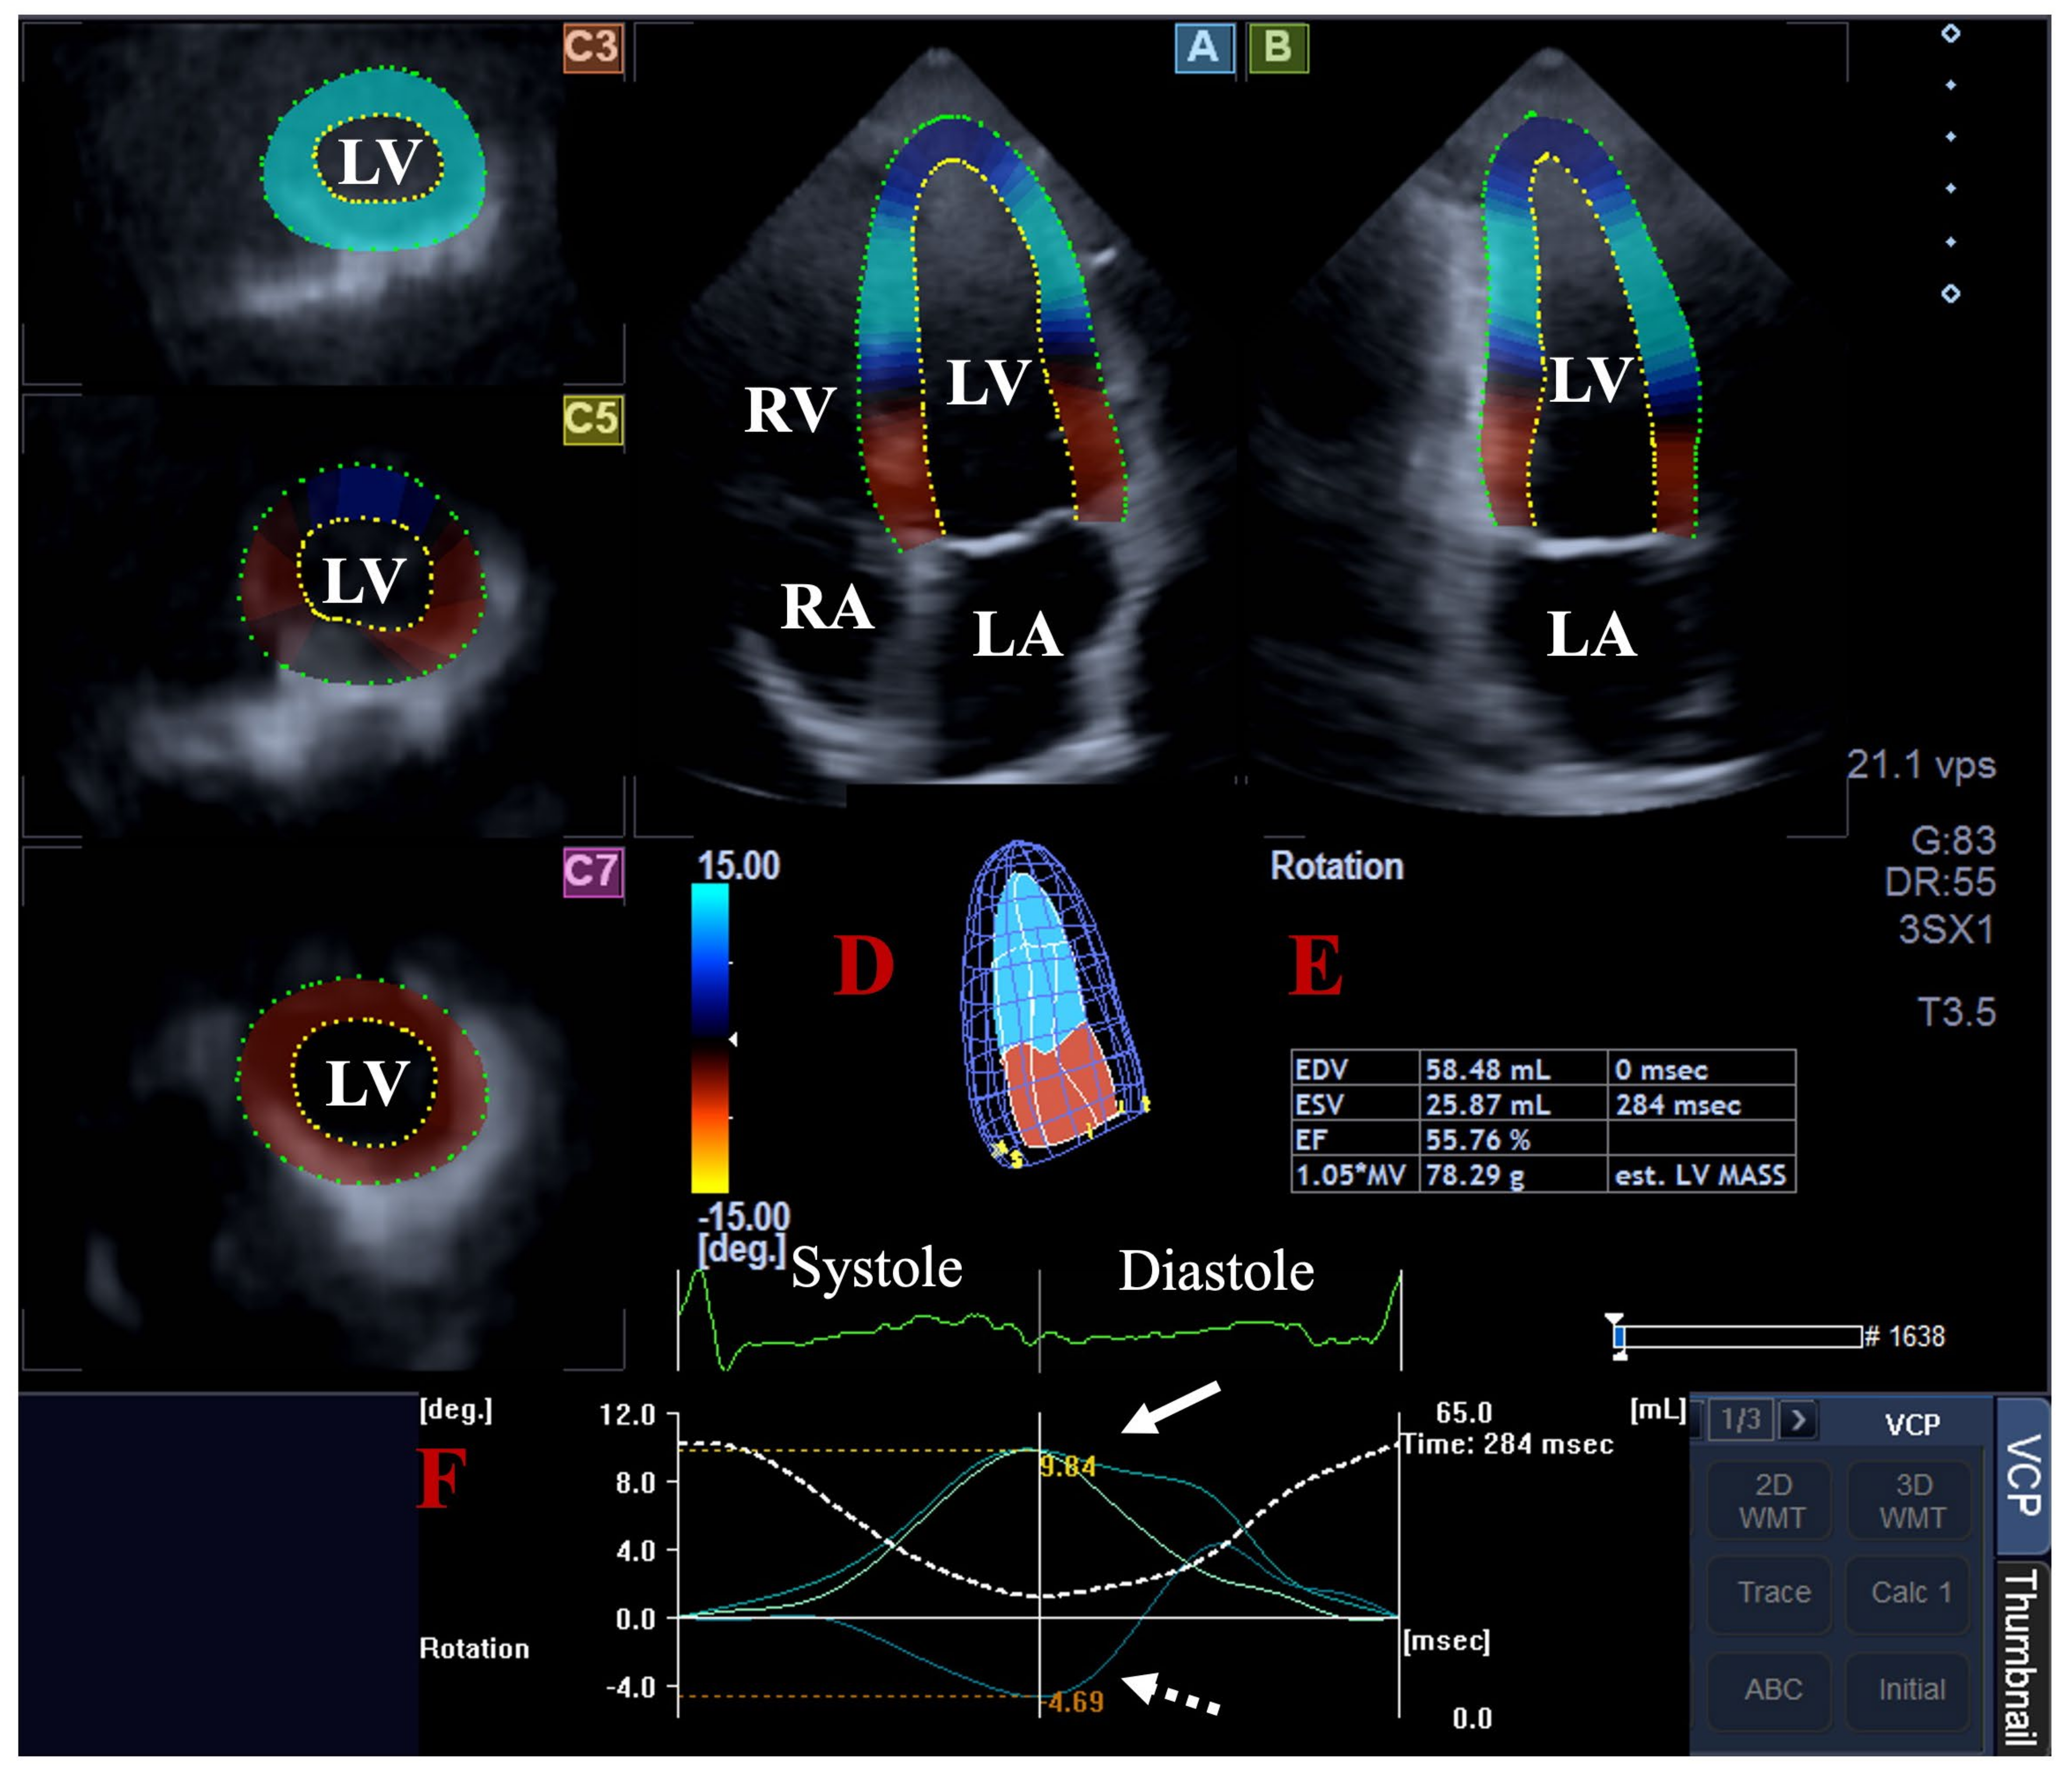

- Kormányos, Á.; Kalapos, A.; Domsik, P.; Lengyel, C.; Forster, T.; Nemes, A. Normal values of left ventricular rotational parameters in healthy adults-Insights from the three-dimensional speckle tracking echocardiographic MAGYAR-Healthy Study. Echocardiography 2019, 36, 714–721. [Google Scholar] [CrossRef] [PubMed]

- Nemes, A.; Kormányos, Á.; Ambrus, N.; Lengyel, C. Complex Relationship of Left Ventricular Rotational Mechanics and Deformation Represented by Strain Parameters in Healthy Adults-Detailed Analysis from the Three-Dimensional Speckle-Tracking Echocardiographic MAGYAR-Healthy Study. J. Clin. Med. 2023, 12, 7389. [Google Scholar] [CrossRef] [PubMed]

- Nemes, A.; Kormányos, Á.; Ruzsa, Z.; Achim, A.; Ambrus, N.; Lengyel, C. Left ventricular rotational mechanics and left ventricular volumes: Is there a relationship in healthy adults?-three-dimensional speckle-tracking echocardiography-derived insights from the MAGYAR-Healthy Study. Quant. Imaging Med. Surg. 2023, 13, 6583–6589. [Google Scholar] [CrossRef]